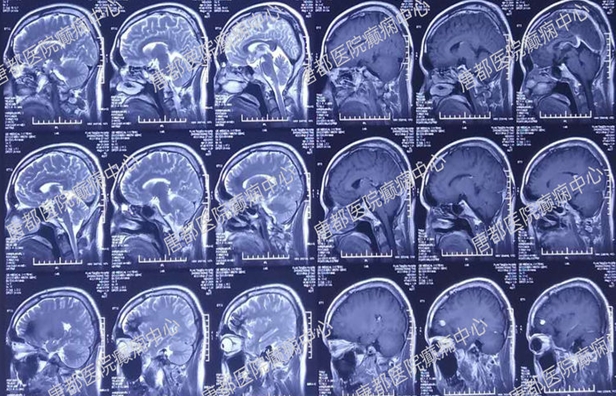

术前核磁检查:

左额叶海绵状血管瘤